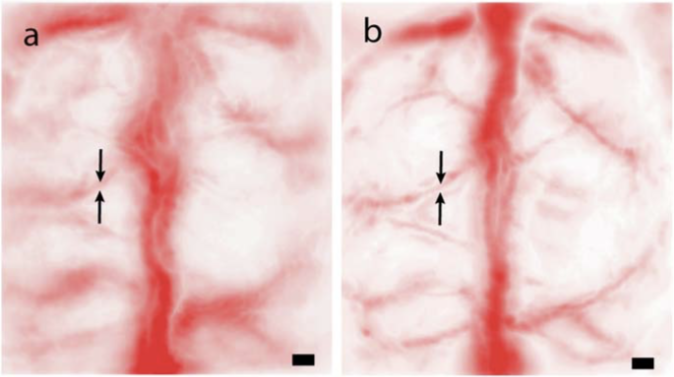

超快多普勒技术被用于成像清醒雪貂的丘脑‐皮层听觉通路(Demené等人,2016a)。作者采用了超快多普勒断层扫描(UFD‐T),该技术简要来说包括以500赫获取的二维功率多普勒图像(每帧由以5500赫发射的11次倾斜平面波发射构成),并结合传感器的平移与旋转(更多细节见(Demenéet al.,2016b))。他们在总体积为 14× 14× 20mm3的空间内实现了100微米的各向同性三维分辨率(图19)。为了获得这些结果,他们对每只雪貂进行了开颅手术,使该方法归类为侵入性,并使用了中心频率为15兆赫的定制微型探头。

超快超声定位显微镜(uULM)在(Erricoetal.,2015)中被提出,其灵感来源于光学定位显微镜的概念( Ehrenberg,2014),通过捕捉由声学造影剂在超过500赫时产生的瞬态信号去相关实现。该技术得益于突破衍射极限,实现了大脑深部的非侵入性亚波长成像。通过分别定位每个微泡中心并累积其位置以重建血管网络,可获得比波长小百倍的超分辨图像(图20)。利用直径为1至3μ米的微泡,因其具有高形变性,能够克服由经典波动衍射理论带来的精度限制,据作者称,该理论在临床应用中的精度限制介于200微米和1mm之间。在传统超声中,分辨率直接与超声频率相关,因而也受穿透深度影响(8)。在超快超声成像(UUI)中,分辨率取决于造影剂和传感器特性:背向散射回波的信噪比、带宽以及波束形成过程中所用阵元数量,据(Errico等人,2015)所述,这些因素可实现 2.5μ米的理论分辨率。作者在减薄颅骨(侵入性方法)条件下,在3毫米深处获得了 10× 8μm 2像素的成像结果,相比传统超声成像分辨率提高了十倍。他们还通过完整颅骨(非侵入性方法)进行了测量,检测到大脑内部深度超过 8毫米处细至20μ米宽的血管。